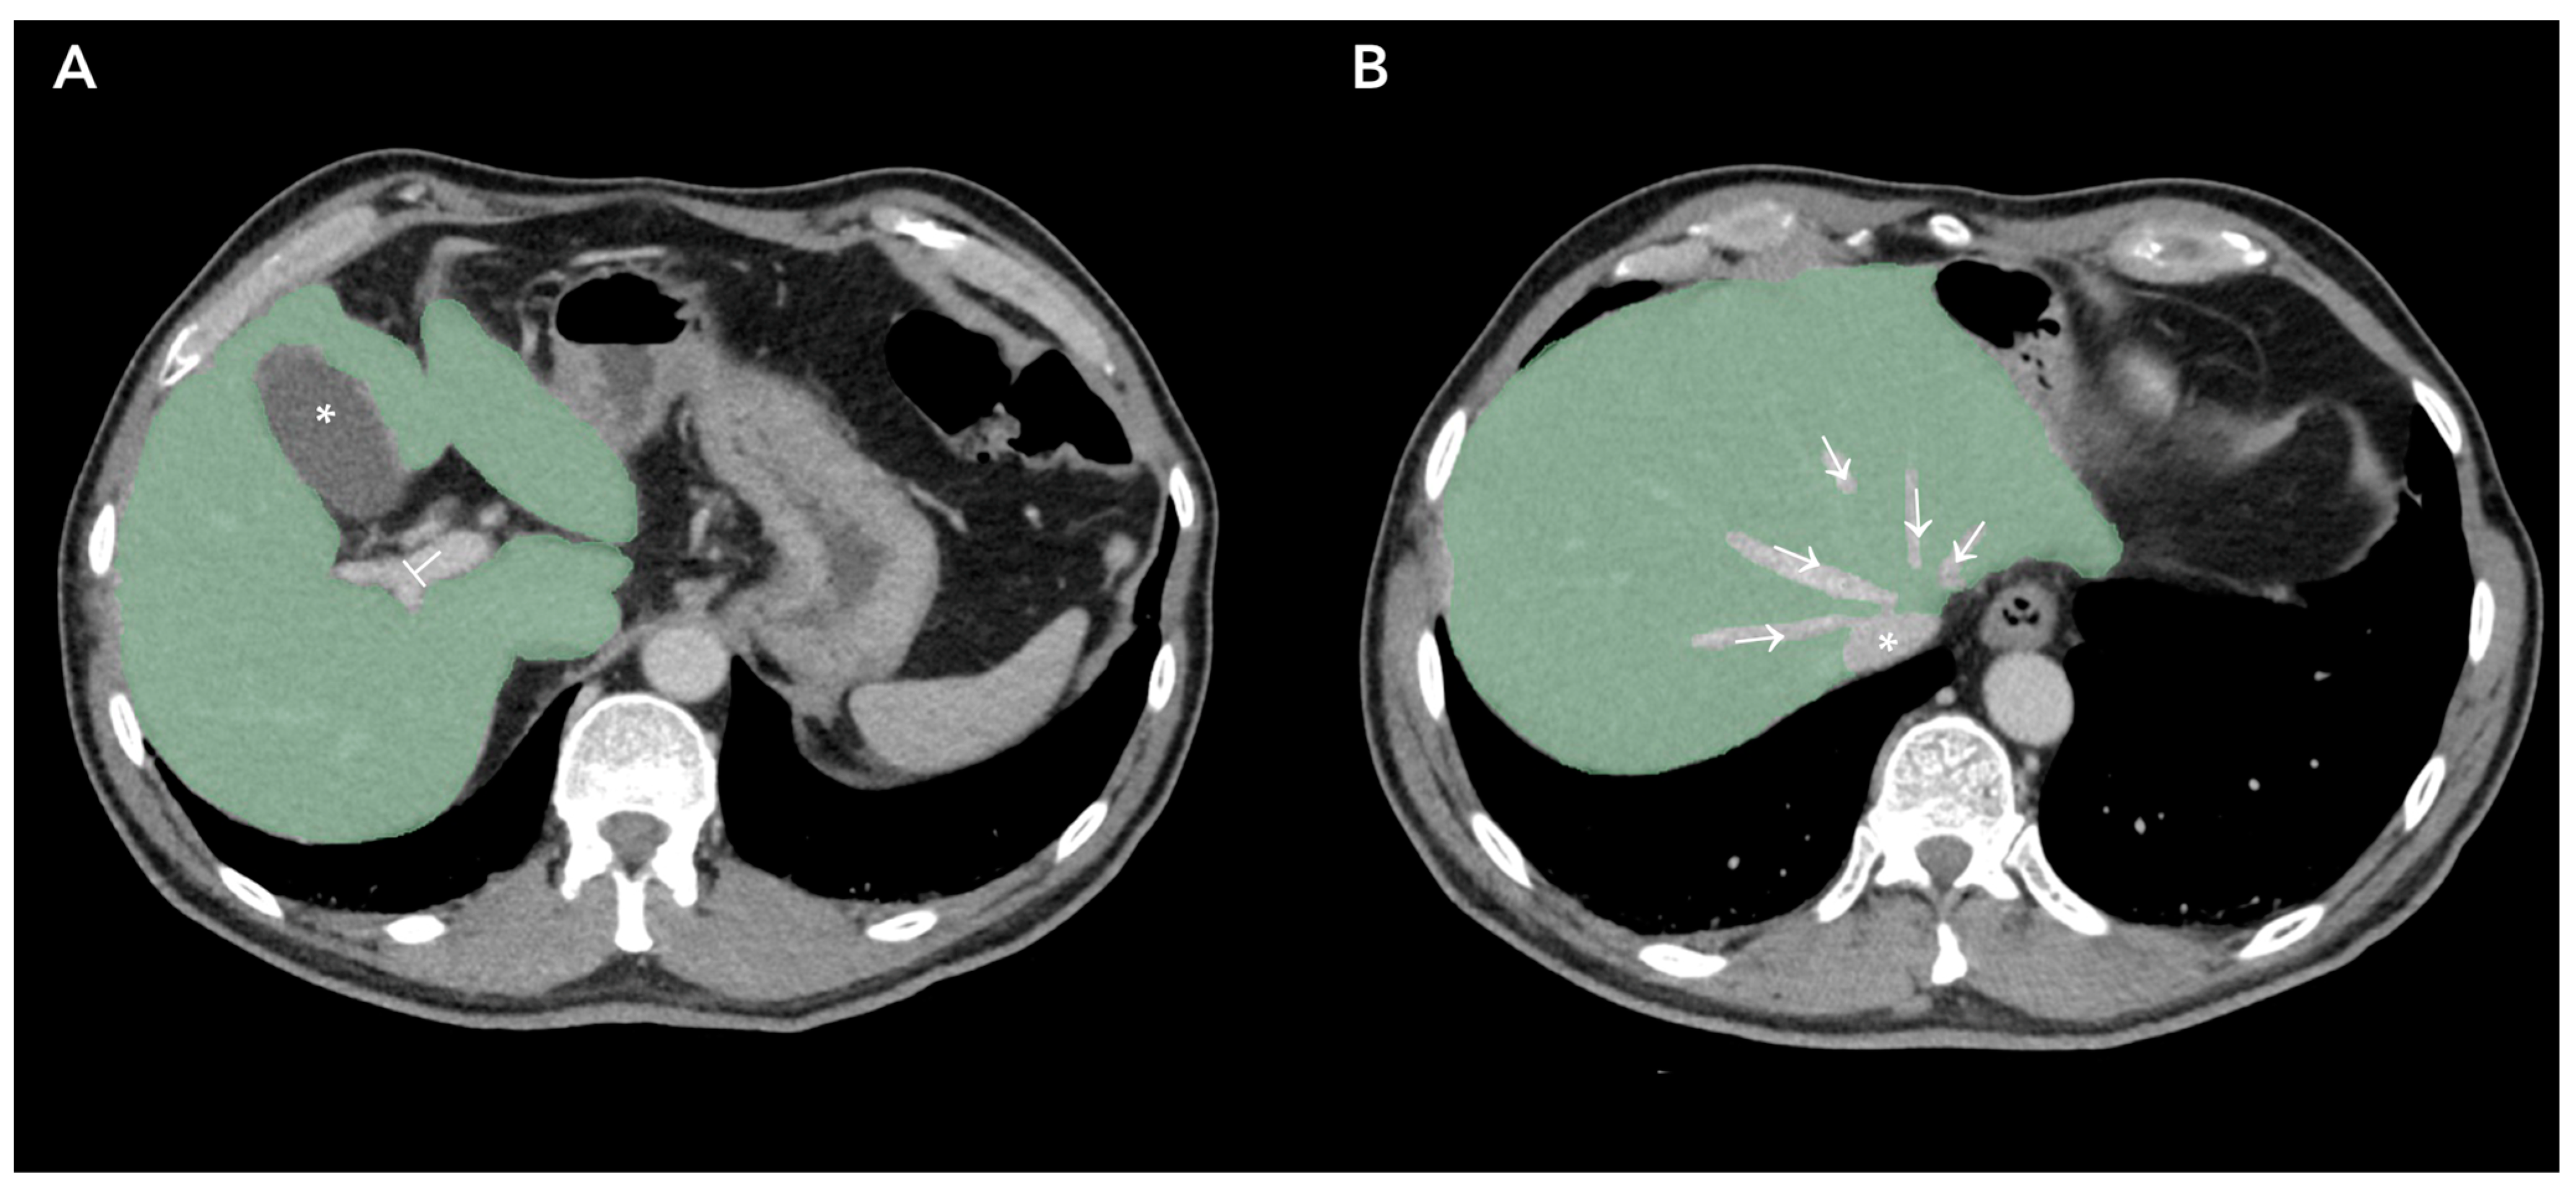

- Rocca, A.; Brunese, M.C.; Santone, A.; Avella, P.; Bianco, P.; Scacchi, A.; Scaglione, M.; Bellifemine, F.; Danzi, R.; Varriano, G.; et al. Early Diagnosis of Liver Metastases from Colorectal Cancer through CT Radiomics and Formal Methods: A Pilot Study. J. Clin. Med. 2021, 11, 31. [Google Scholar] [CrossRef] [PubMed]

| Rocca et al. [21] | 2021 | Formal methods | 30 | CRC | NA | NA | CT | 3–48 months |

| Rocca et al. [21] | NA | 22 | 93.3% | 100% | 100% | 77.8% | NA | NA | NA |